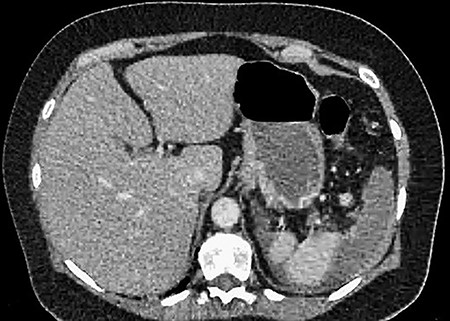

A 61-year-old female presented to a regional hospital with a 3-week history of intermittent diarrhoea, vomiting and generalized abdominal pain. She had a diffusely tender abdomen but was not peritonitic, and was shocked with a heart rate of 110 beats per minute, blood pressure of 89/45 mmHg and was peripherally cool. Her blood tests revealed a lactate of 7.2 mmol/L, which worsened to 7.8 mmol/L during resuscitation with intravenous fluids, and white cell count was 30.9 × 109/L, with an international normalized ratio (INR) of 1.4. She had an acute kidney injury with a creatinine of 119μmol/L and estimated glomerular filtration rate (eGFR) of 43 mL/min/1.73m2. Computed tomography (CT) revealed extensive thickened loops of non-enhancing small bowel with pneumatosis, moderate free fluid and a large splenic infarction. There was extensive thrombosis of the splenic vein and superior mesenteric vein extending into the portal vein to the level of the porta hepatis. Her background history included factor V Leiden and protein S deficiency, for which she had been non-compliant with warfarin during this illness. She had no surgical history (Figs. 1–5).

CT showing complete occlusion of the portal vein at the level of the porta hepatis.

CT showing an area of splenic infarction due to venous ischaemia.